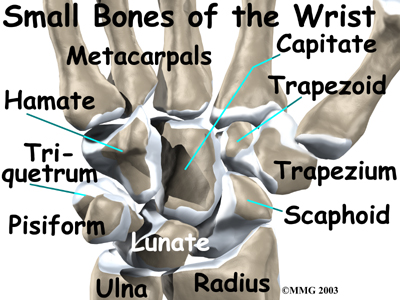

The wrist is made up of eight separate small bones, called the carpal bones. The carpal bones connect the two bones of the forearm, the radius and the ulna, to the bones of the hand. The metacarpal bones are the long bones that lie mostly underneath the palm. The metacarpals are in turn attached to the phalanges (the bones in the fingers and thumb).

One reason that the wrist is so complex is that every small bone forms a joint with the bone next to it. This means many small joints make up the wrist joint. Ligaments connect all the small bones to each other, and to the radius, ulna, and metacarpal bones.